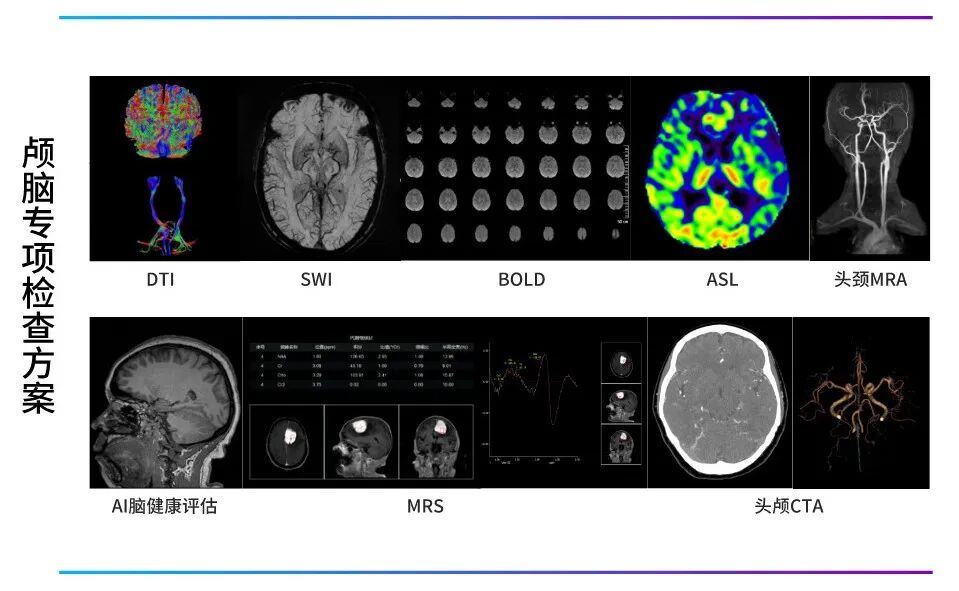

成都影和医学影像诊断中心配置了联影「光梭3.0T磁共振」,凭借着国际领先水平的超高端科研型3.0T超导磁共振,拥有血管成像( MRA/MRV)、水成像( MRCP/MRU)、弥散成像(DWI)、弥散张量成像(DTI)、灌注成像(PWI)、波普成像(MRS)、磁敏感加权成像(SWI)及高级心血管造影软件包等。